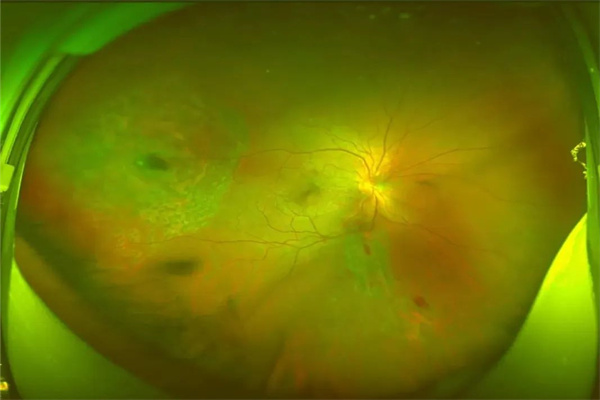

接診后,眼科楊清清主治醫(yī)師仔細對王申進行眼部檢查后發(fā)現(xiàn),他的右眼眼球破裂,球內(nèi)積血較多,懷疑眼球內(nèi)存留異物;而后,眼眶CT及歐堡掃描激光眼底照相結果顯示,一個直徑約4mm的金屬異物擊穿角膜、前房、虹膜、晶狀體、玻璃體并嵌頓于顳側(cè)視網(wǎng)膜上,也就是說,異物直接把眼球中所有的重要組織全部貫通。最重要的是人體中含水量最高的器官則是眼球,眼球內(nèi)組織絕大部分都是由水分構成,異物在眼內(nèi)很快便會生銹、粘連、牽拉,若不及時取出異物手術治療,可能導致眼內(nèi)感染、眼球萎縮,最終失去光明,且另一只健眼還有發(fā)生交感性眼炎的可能性。

手術中,眼科團隊在清除王申右眼球內(nèi)積血后發(fā)現(xiàn),金屬異物嵌頓于視網(wǎng)膜內(nèi),視網(wǎng)膜部分撕裂,實際情況比原先預料的更為嚴峻。